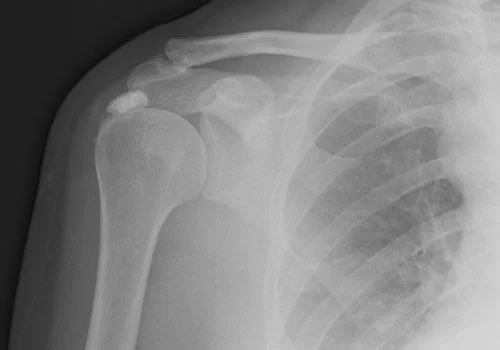

X-rays are a type of radiation that can produce an image of the inside of your body, a little like a photograph.